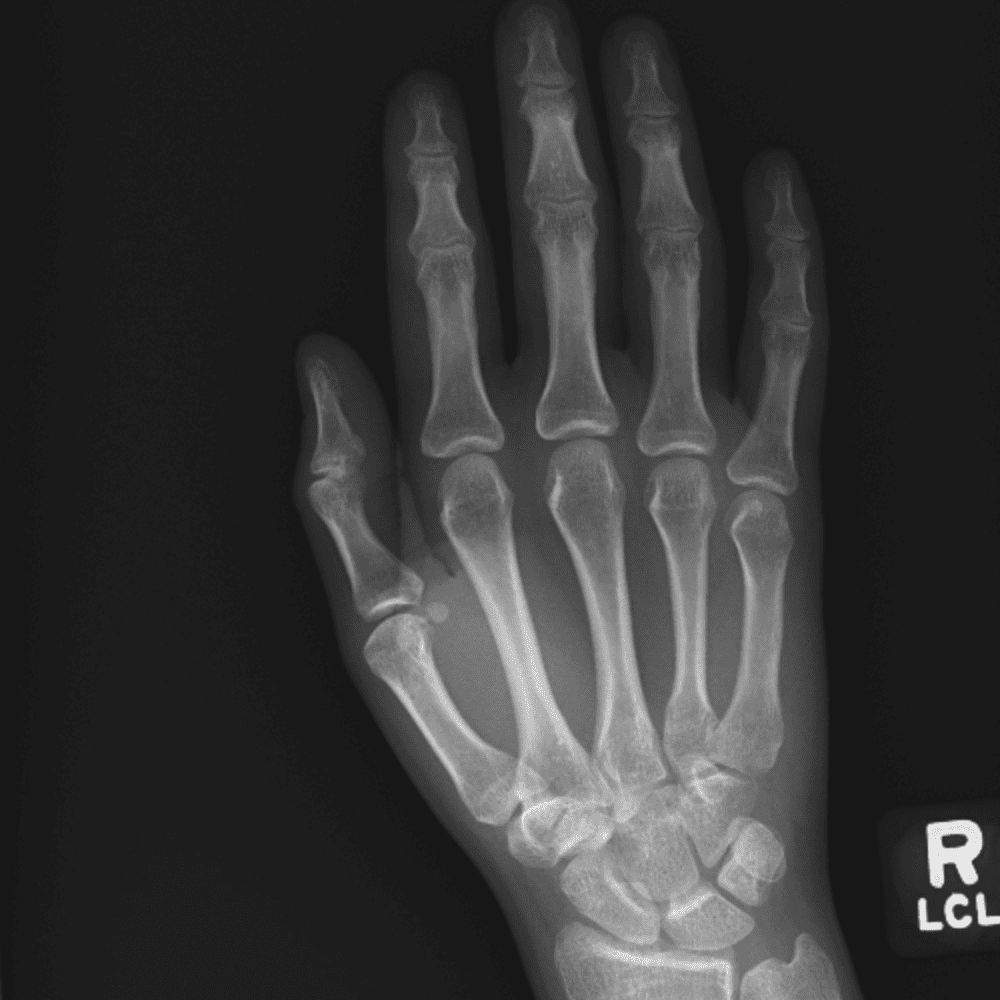

Simuliert den Dienst durch subtile oder schwierige Fälle und einige Normalbefunde.

30 Fälle